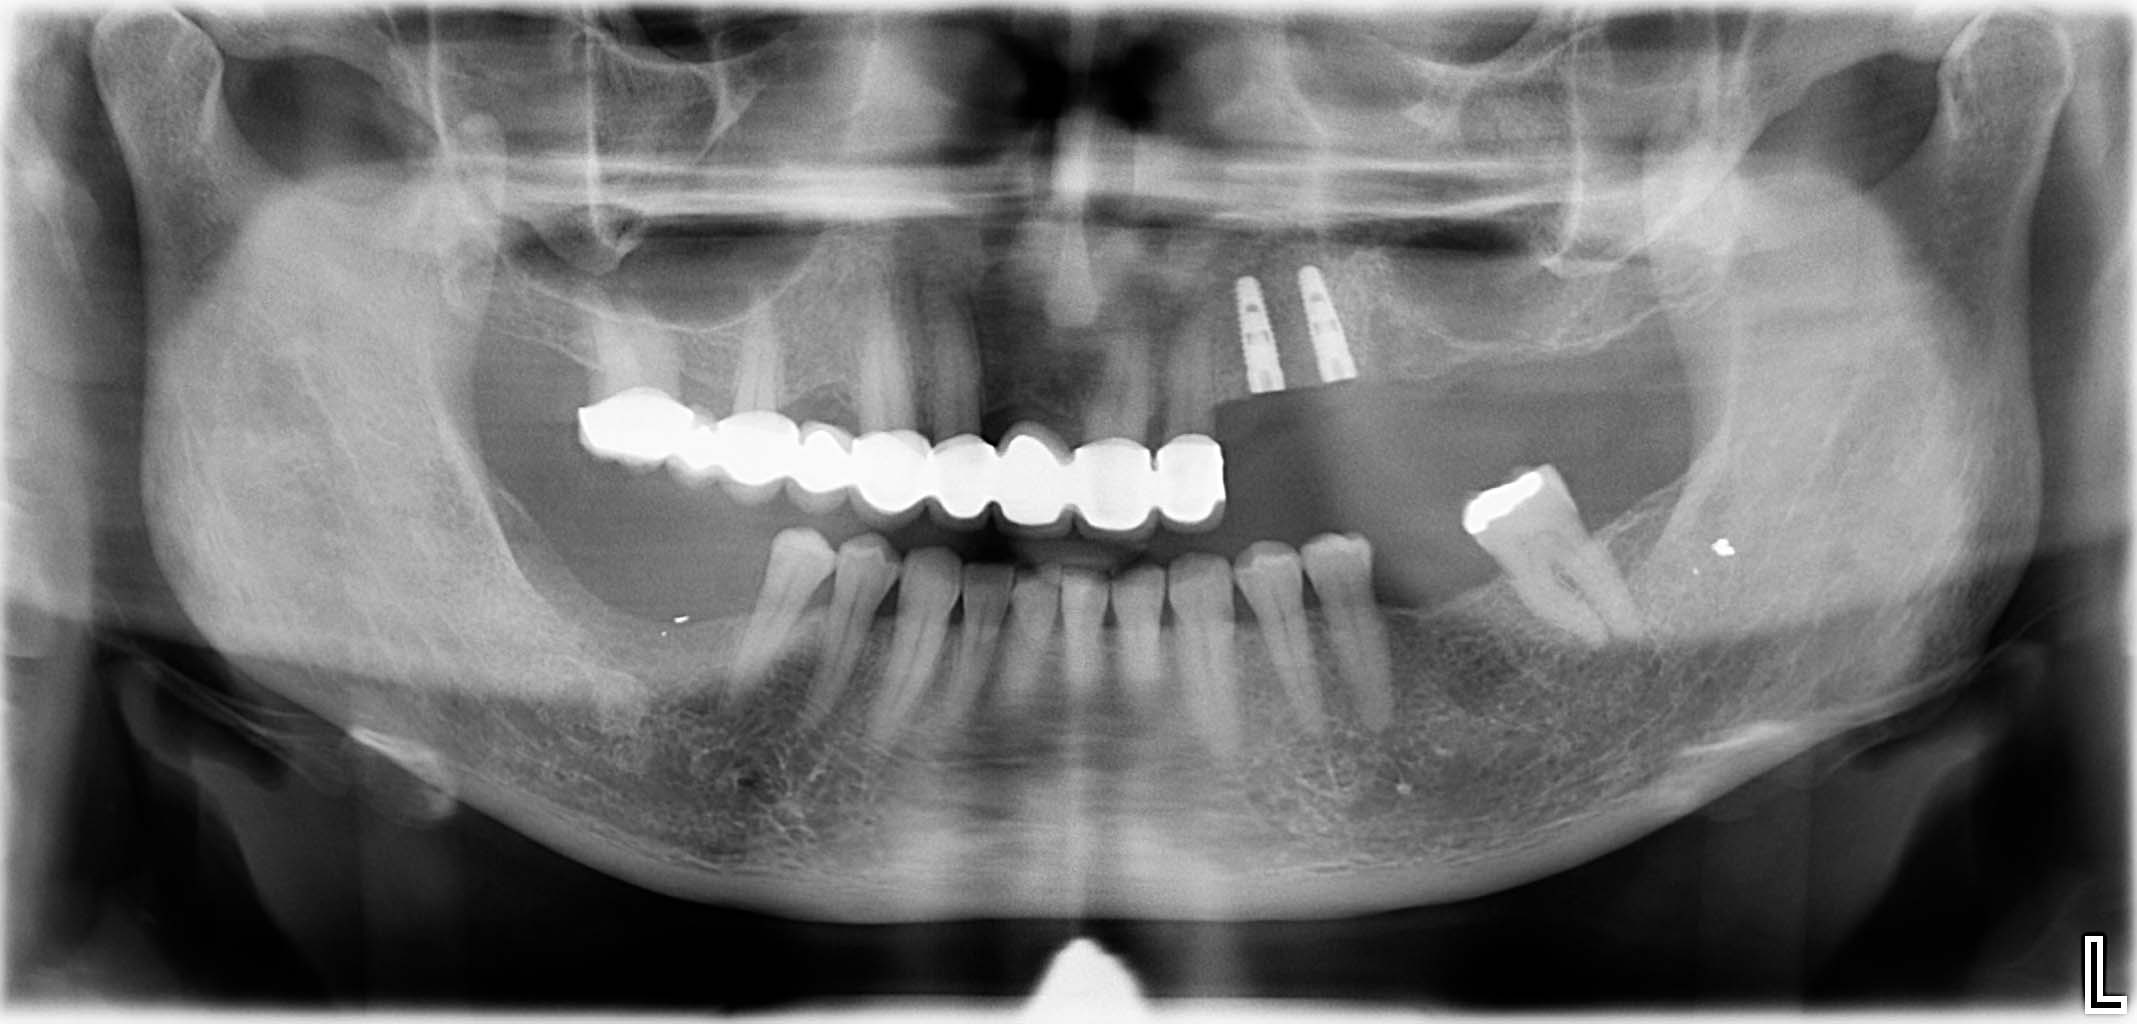

Ausgangssituation: Zahn 36 mit apikaler Beherdung, nicht erhaltungswürdig

Erfolgreich implantierte Patientenfälle (klinische Fotos)